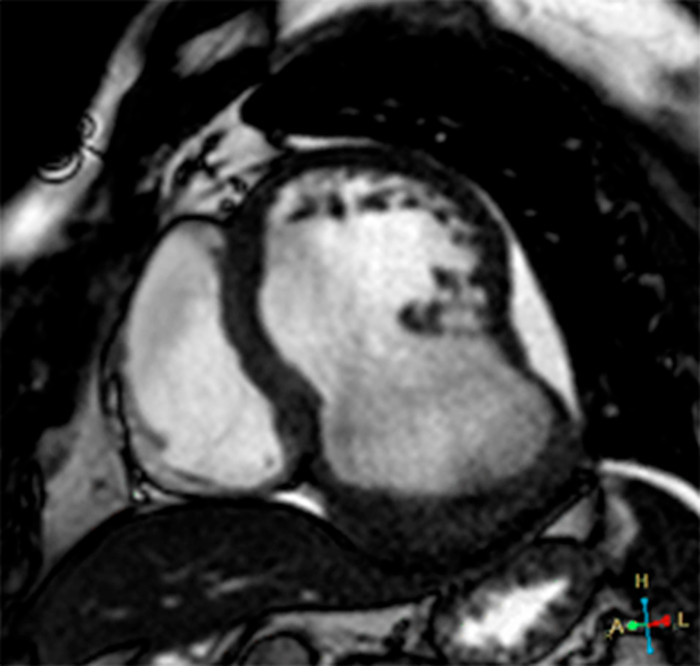

Se presenta el caso de un paciente de sexo masculino, de 50 años de edad, derivado por infarto agudo de miocardio de cara inferior, 25 días previos a la consulta, no habiendo sido revascularizado. Se encontraba clínicamente estable. Debido a presentar mala ventana acústica, se solicita la realización de una resonancia magnética cardíaca con contraste no ferromagnético (gadoterato de meglumina). Bajo esta técnica, se observa una cavidad en comunicación con la cámara ventricular izquierda, de cuello ancho y la presencia en su interior de un trombo que tapiza su superficie (Fig. 1, dos cámaras y Fig. 2, eje corto). Tras la administración del contraste, se observa realce tardío a los 10 minutos de la pared de esta estructura (Fig. 3, eje corto), certificando la naturaleza aneurismática y descartando el pseudoaneurisma ventricular. Debido a su tamaño, ante la posibilidad de desarrollo de falla cardíaca o evento embólico, se decide su intervención quirúrgica para plástica ventricular certificando la anatomía patológica la naturaleza fibrótica de su pared.